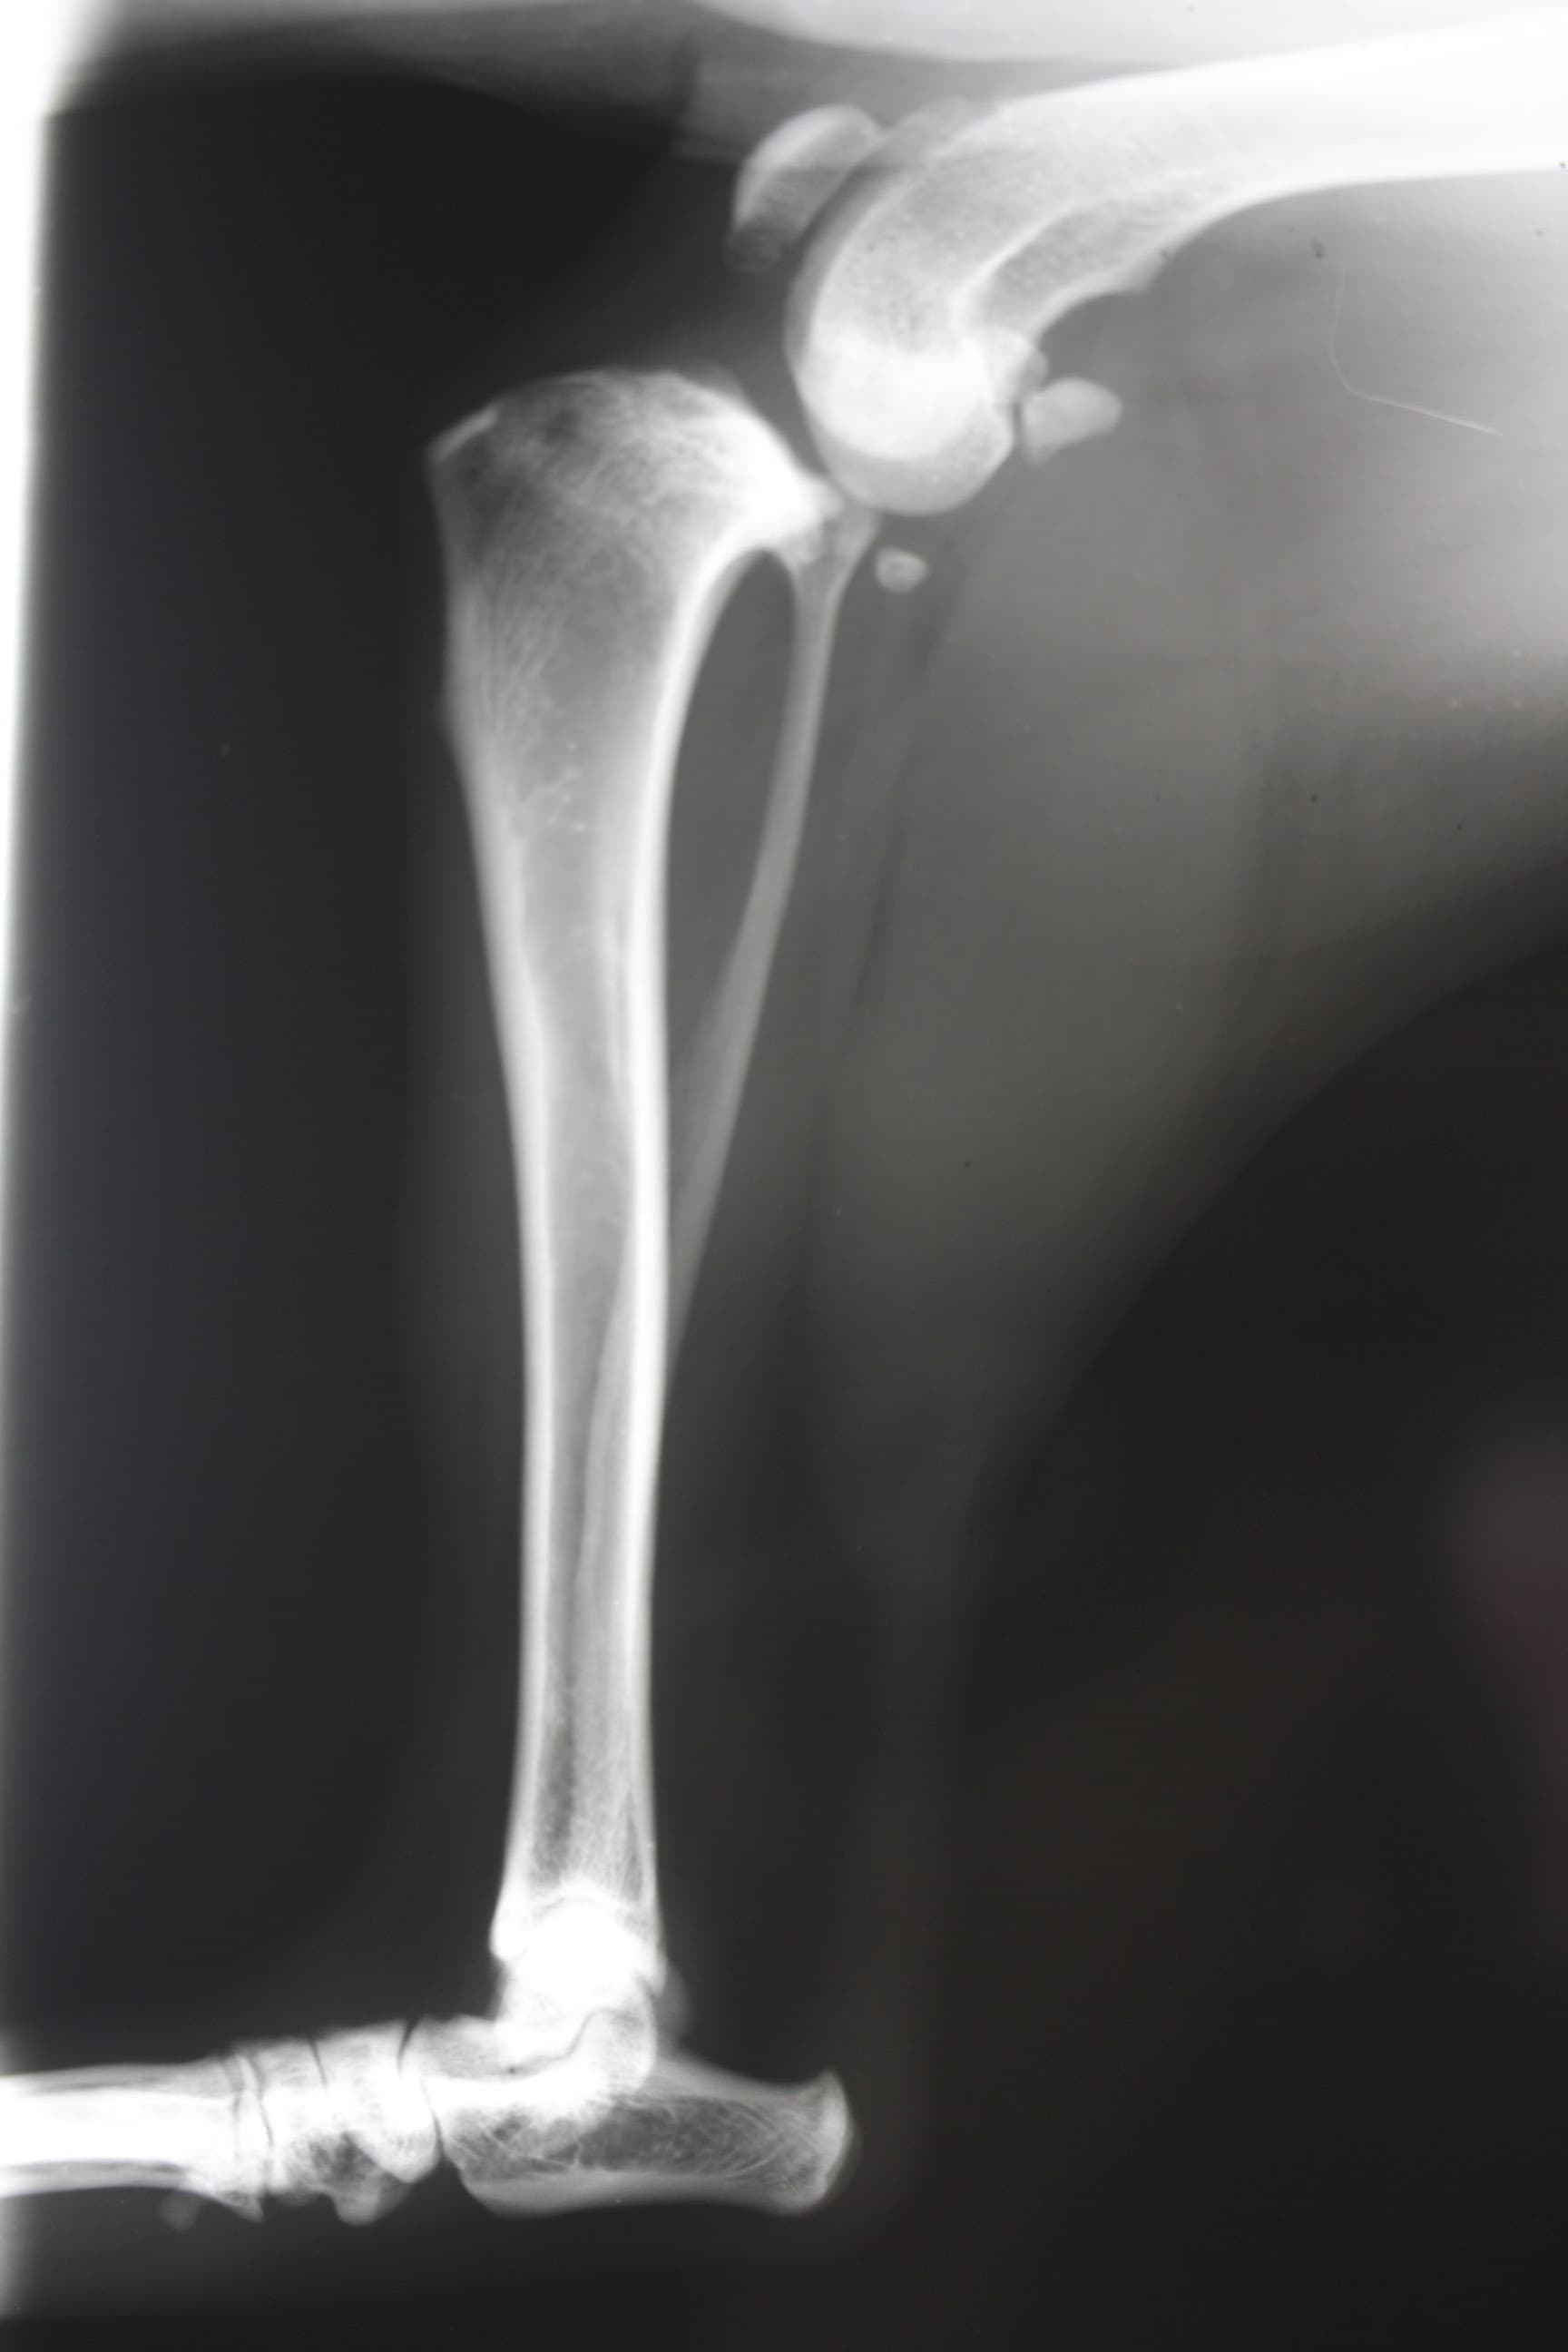

レントゲン写真(後ろ足)

脛骨(スネの骨)の前方変位があります。この靭帯を手術でつなげることはできません。まずは、膝関節の外側に丈夫な糸をかける手術をします。